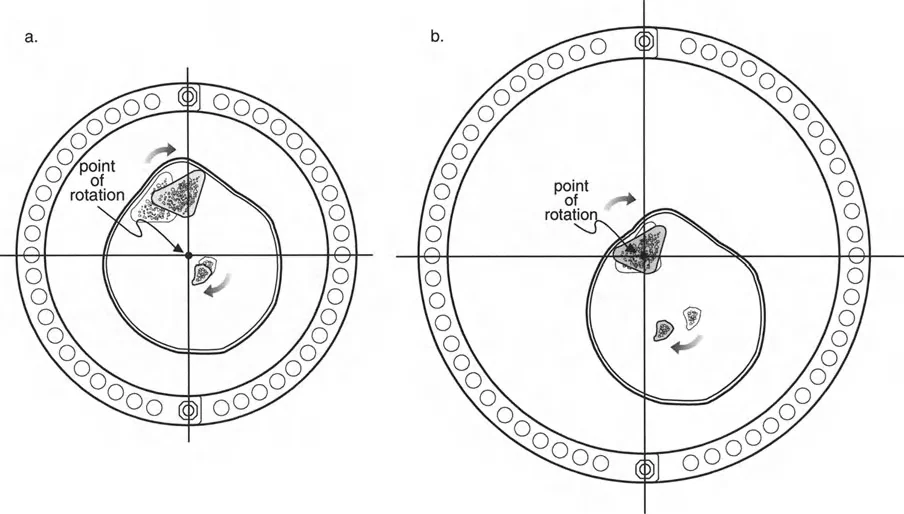

قيود الأسلاك والدبابيس في القاعدة 2

لتحقيق هذه الترجمة الضرورية والمقصودة بسلاسة باستخدام إطار دائري كامل الأسلاك، يلزم استخدام أسلاك الزيتون المعاكسة (counter-opposed olive wires). تعمل أسلاك الزيتون كقوى سحب ديناميكية، تسحب قطعة العظم على طول الحلقة أثناء فتح المفصلات. بدون أسلاك الزيتون، سيبقى العظم ثابتًا بينما تتحرك الحلقة عبر الأنسجة الرخوة، مما يسبب نخرًا شديدًا في الجلد.

على العكس من ذلك، إذا تم استخدام دبابيس نصفية (مسامير شانز)، فإنها تقيد العظم بطبيعتها بالحلقة. نظرًا لأن الدبابيس النصفية هي أذرع صلبة (مثبتة من طرف واحد بالحلقة ومغروسة في العظم من الطرف الآخر)، فإنها لا تسمح للعظم بالانزلاق على طول محور السلك. هذا يجعل أسلاك الزيتون غير ضرورية للترجمة في منشآت الدبابيس النصفية، ولكنه يتطلب من الجراح التأكد من أن الدبابيس النصفية قوية بما يكفي (عادةً دبابيس بقطر 5 مم أو 6 مم مطلية بهيدروكسي أباتيت) لتحمل لحظات الانحناء الناتجة عن الترجمة.